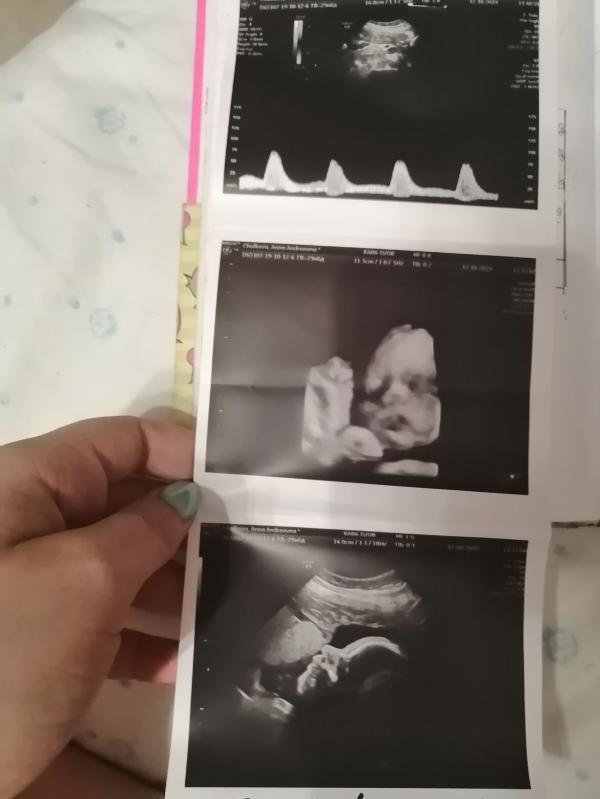

Была сегодня на УЗИ, сказали что все хорошо, но будет крупненьким). Срок беременности уже 34 недельки! 🙃. Наверное у многих с беременностью появился злейший враг "растяжки". очень замучилась с ними на животе☹️!!!

#34недели